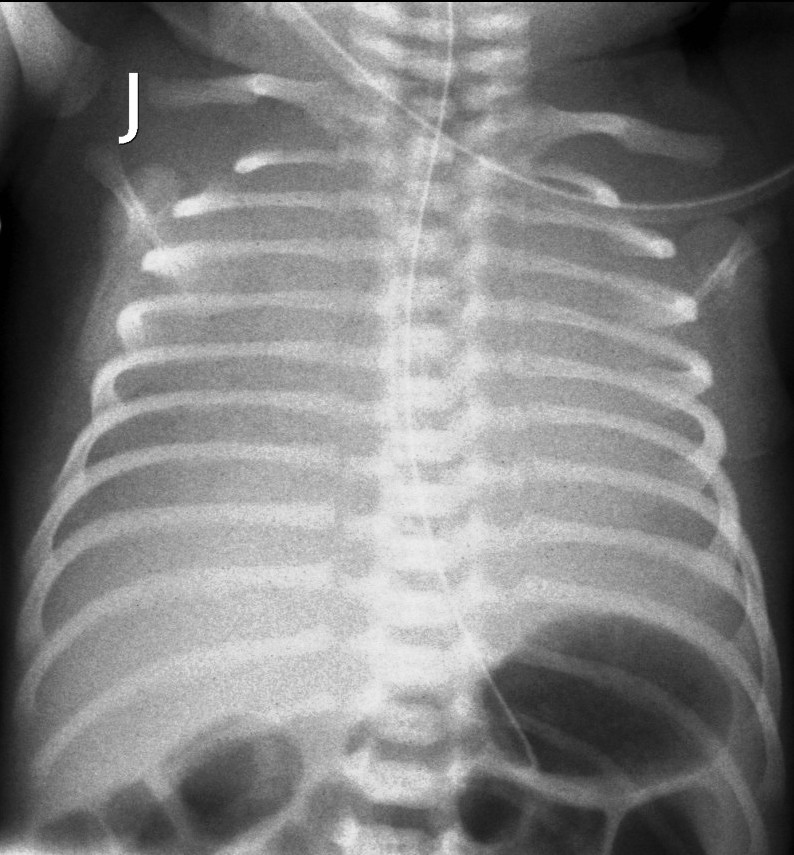

X-ray examination: an X-ray absorbent tube is visible in the obstructed diverticula of the esophagus. In cases of a lower fistula, the intestines are aerated, the accompanying costal and vertebral abnormalities can also be observed.

10.The tube inserted in the esophagus turns back in the height of the 4th Thoracic vertebra, the intestines are filled with gas. Esophagus atresia with lower fistula.

11 The tube inserted in the esophagus turns back in the height of the 2nd Thoracic vertebra. The abdomen is gasless. Esophageal atresia without fistula.